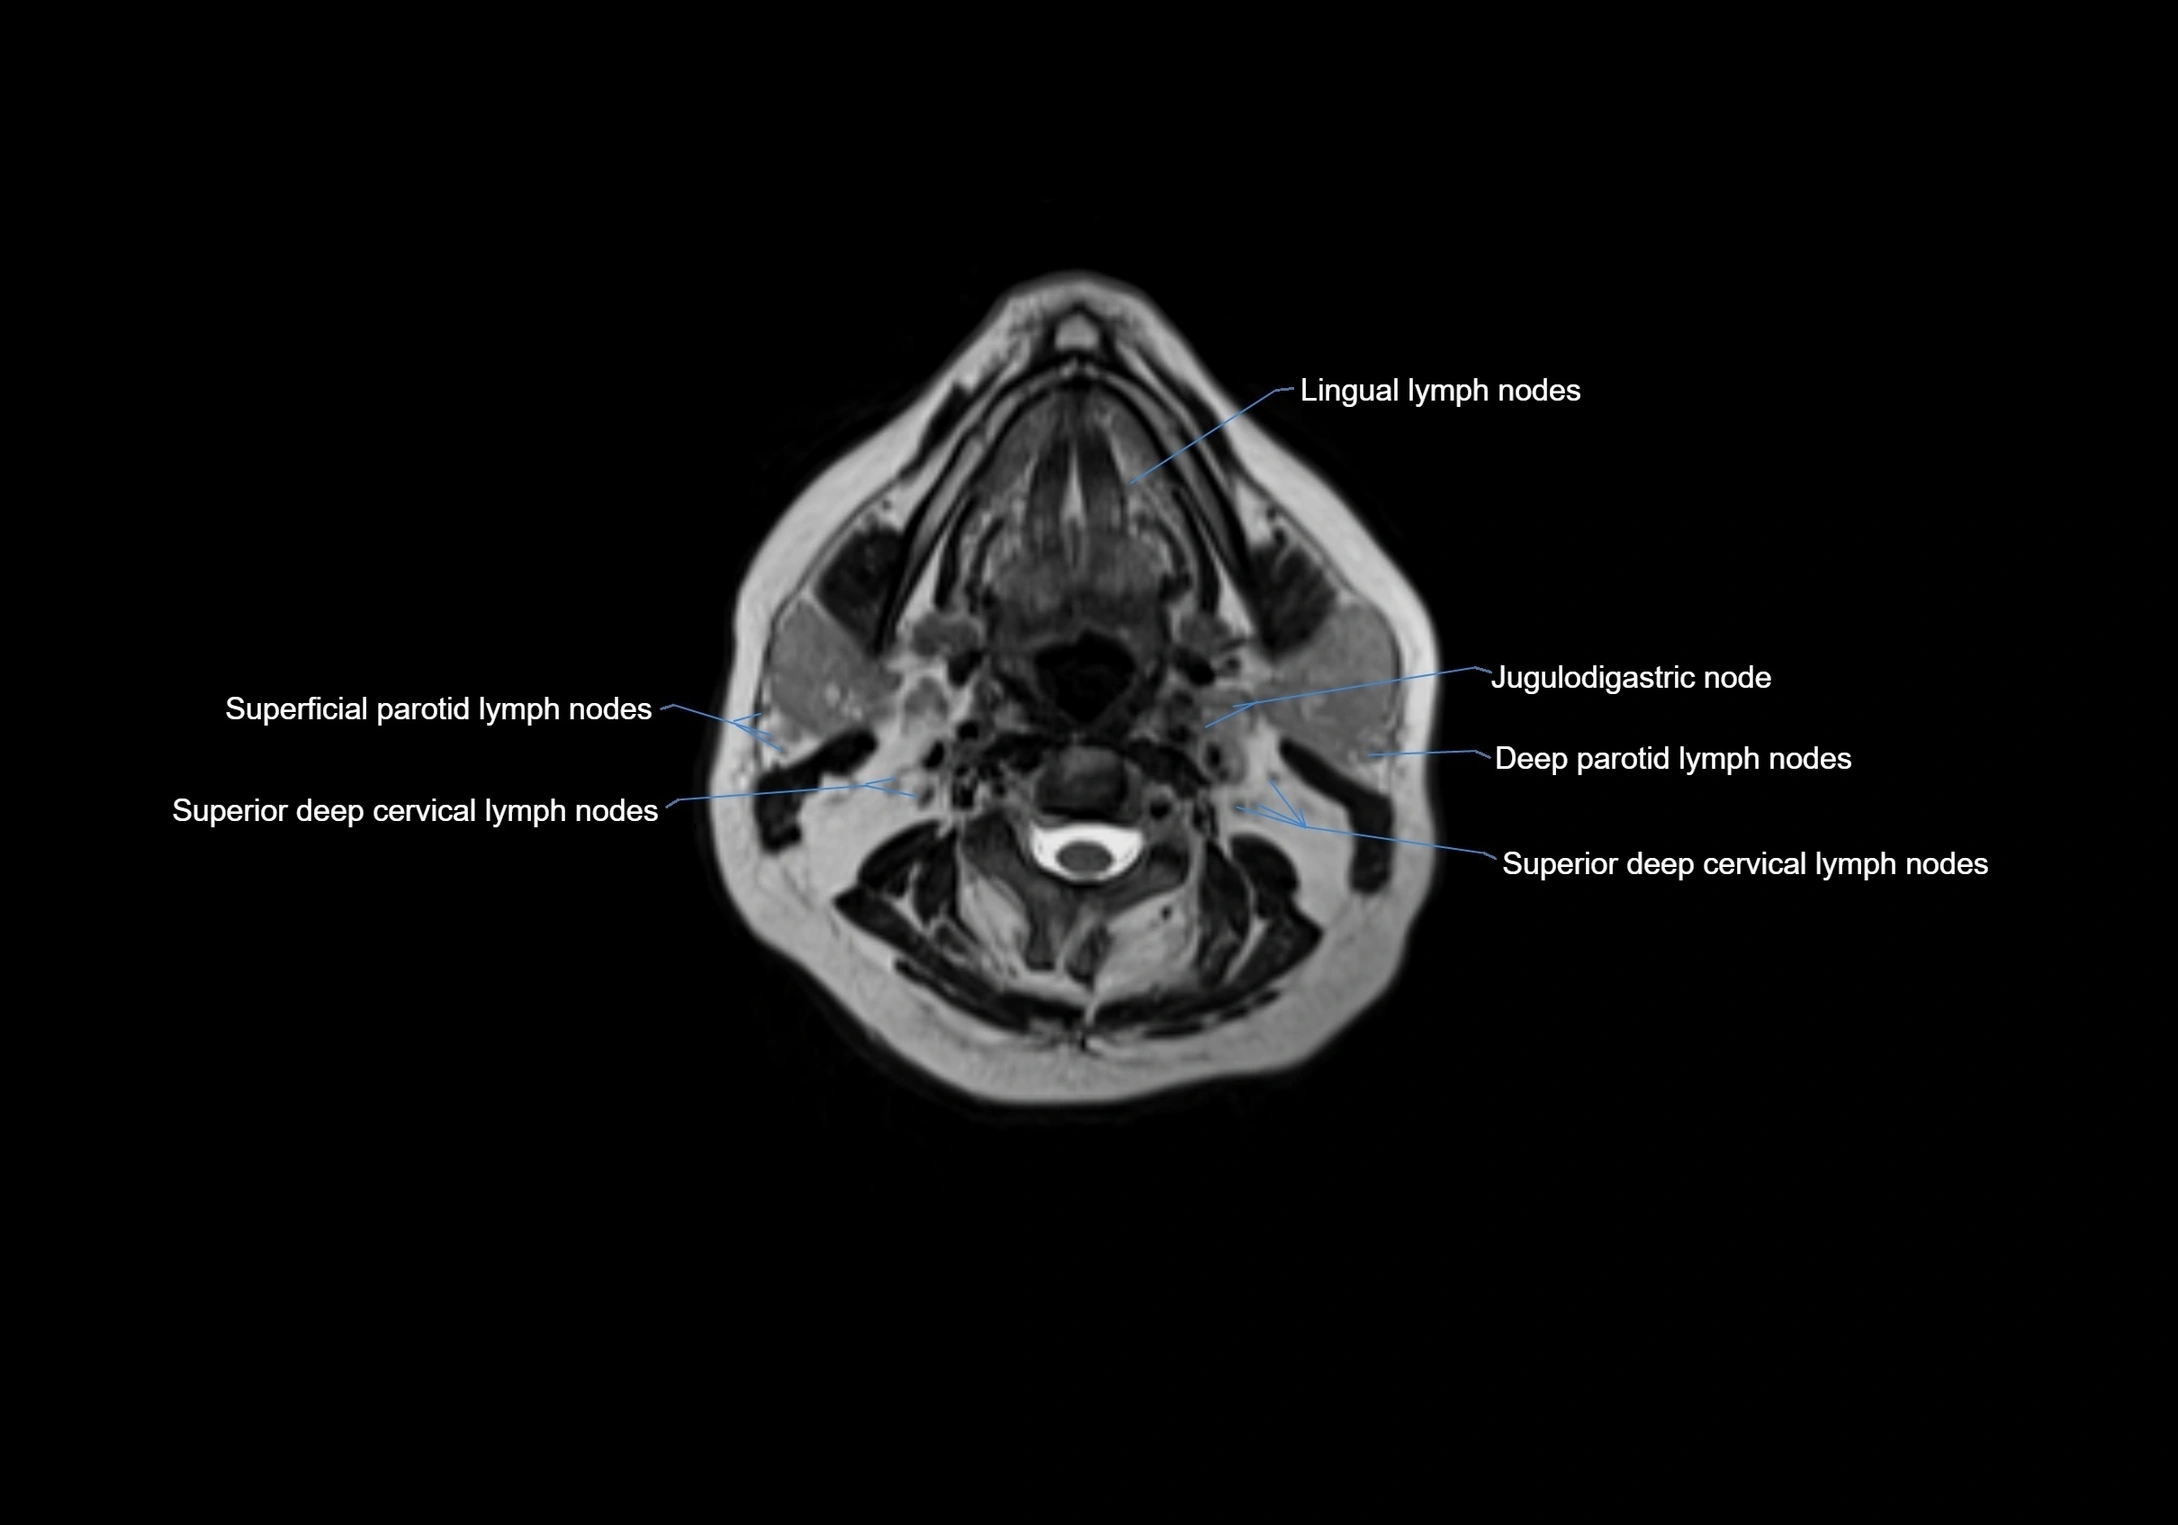

Accessory lymph nodes are small, secondary lymph nodes located along the main facial and cervical lymphatic chains, often adjacent to primary lymph nodes, such as preauricular, submandibular, or occipital nodes. They are typically less than 5 mm in diameter, embedded within subcutaneous fat or connective tissue, and may be variable in number and location. These nodes provide additional filtration and immune surveillance for lymph collected from the face, scalp, and neck regions. Accessory lymph nodes are usually non-palpable in healthy individuals but may enlarge in response to infection, inflammation, or metastasis, making them clinically significant.

Location

• Found along primary lymph node chains, including preauricular, submandibular, parotid, and occipital regions

• Embedded in subcutaneous fat or superficial fascia, often lateral or posterior to primary nodes

• Variable in number; may occur unilaterally or bilaterally, depending on individual anatomy

MRI Appearance

T1-weighted images:

• Normal accessory nodes appear as small, oval hypointense to intermediate signal structures within subcutaneous fat

• Surrounded by hyperintense fat, enhancing contrast for visualization

• Pathological nodes may appear enlarged or rounded, sometimes with cortical thickening